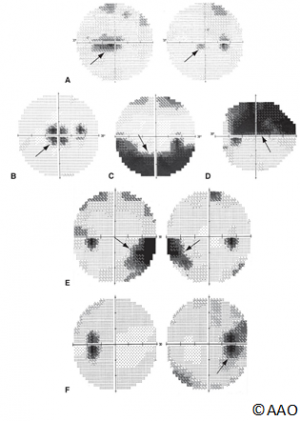

- Variable visual field loss in the affected eye in an optic neuropathy pattern with visual field loss of papilledema in the fellow eye (e.g., enlarged blind spot, nerve fiber layer loss)

- Variable visual acuity and/or visual field loss in each eye

- Relative afferent pupillary defect (RAPD) may be present in worse affected eye

- Optic atrophy in prior affected eye

- Optic disc edema (sector or diffuse) in acutely affected eye